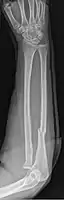

Monteggia Fracture (type of ulna fracture)

Fractures of the ulna can occur at different levels of the bone: near the wrist, in the middle or near the elbow.[2] The fracture may be confined to the ulna or accompanied with damage to the radius or the wrist or elbow joints.[2]